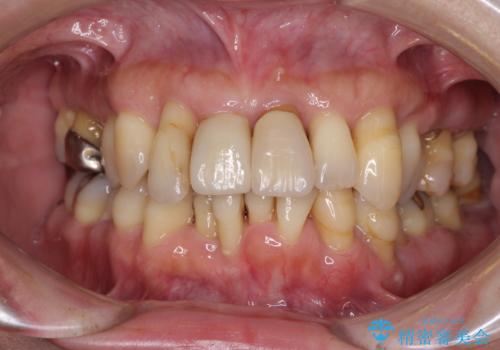

- 黄色みのある前歯のセラミックを、明るい色に替えたいとのことで来院された患者様です。

透明感がないことも気になっていたため、オールセラミッククラウンでは透けてしまう可能性のある金属の土台をファイバーコアに置き換え、1トーン明るいクラウンにて仕上げていくこととしました。